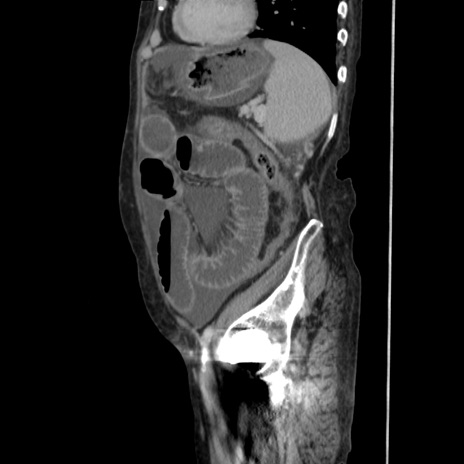

症例31(矢状断像)

【症例】80歳代 女性

【主訴】腹部膨満感

【現病歴】他院にて肝硬変にてフォロー中。1週間前から便秘、腹部膨満感、臍部腫瘤あり受診となる。

【既往歴】肝硬変

【身体所見】腹部膨隆あり、皮膚変化なし、疼痛なし。

【データ】WBC 4600、CRP 0.25